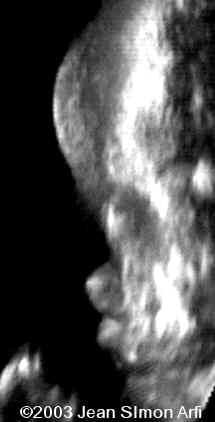

The following images were obtained in from second trimester fetus. The head demonstrated a cloverleaf skull, frontal bossing, proptosis

The most striking features were :

1. craniosynostosis with

2. cloverleaf skull and

3. severe ocular proptosis.

The fetus after delivery: The same findings can be observed: